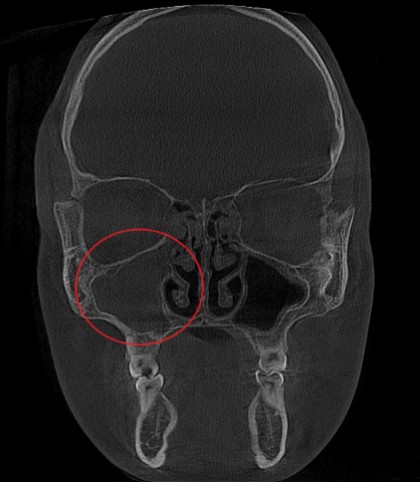

Проведена компьютерная томография околоносовых пазух, которая подтвердила наличие правостороннего гемисинусита (воспаление нескольких пазух с одной стороны), как следствие периодонтита зуба 1.6.

Представлено КЛКТ околоносовых пазух до начала лечения. Выделена зона воспаления пазух.